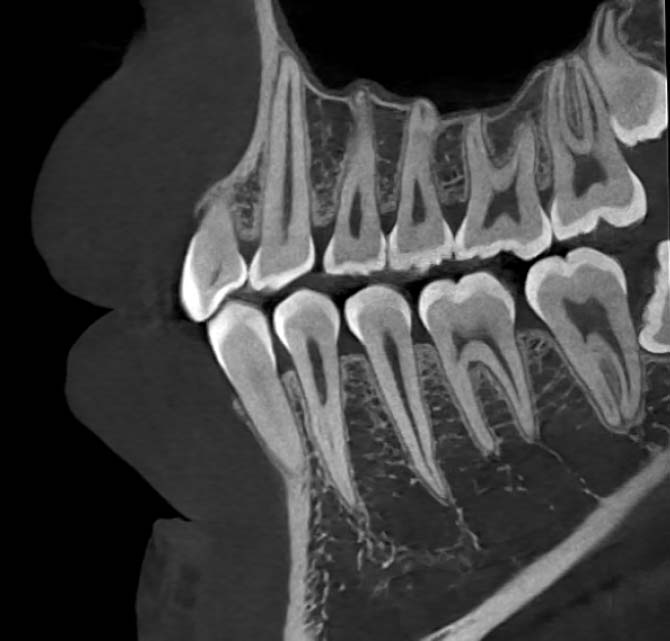

Comprehensive 3D volumetric images, supporting interactive rotation from any angle and local magnification, along with multi-slice views. This helps doctors observe the shape and spatial relationships of various anatomical structures, facilitating communication between doctors and patients.

Narrower X-ray beam angle By utilizing helical scanning imaging technology, the Hirox-O scans with a small cone angle X-ray, effectively reducing cone beam artifacts and delivering clearer images.

Base on physics-driven, allowing for artifact elimination at the physical level, ensuring that real image details are preserved.

High-definition low-redundancy reconstruction algorithm Fully utilizing the redundancy in scanning geometric data and parallel computing via GPU allows for faster and more accurate image reconstruction.

Low dose imaging algorithm The low-dose imaging algorithm can reduce radiation exposure for patients while maintaining image clarity.

28lp/cm spatial resolution Tissue details are clearly visible

28lp/cm spatial resolution

Tissue details are clearly visible